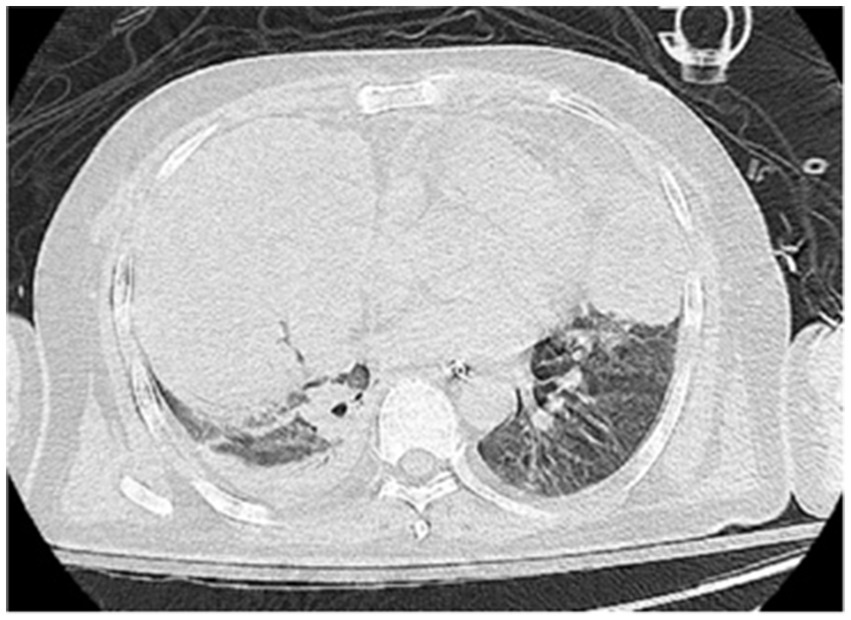

On the sixth day following VV-ECMO treatment, a favorable outcome was observed as the sputum culture yielded negative results (IL-6: 100 pg./mL, CRP: 195 mg/L), and there was a significant decrease in inflammatory indicators. The patient’s pulmonary condition demonstrated a marked improvement relative to the previous state, prompting a change in the antibiotic regimen to cefoperazone sodium-sulbactam sodium (2 g) administered every 8 h and voriconazole (200 mg) given via nasogastric feeding every 12 h. Concurrently, the patient’s oxygenation index improved, and lung function gradually recovered. This was based on the patient’s improved oxygenation and gradually recovering lung function, which indicated that the patient might be able to tolerate the discontinuation of ECMO support. The ECMO parameters were gradually titrated downwards, and the ECMO was weaned on the ninth day post-VV-ECMO treatment. At this point, the lung condition has improved significantly compared to before (Figure 2, and IL-6: 53 pg./mL, CRP: 202 mg/L). Given the patient’s persistent difficulty with extubation, the presence of retained respiratory secretions was suspected. Thus, percutaneous tracheotomy was performed on the second day post-ECMO weaning to alleviate the patient’s dyspnea symptoms. To further assess the patient’s lung condition following ECMO weaning, a repeat chest CT scan was performed on the fourth day after the procedure. The imaging revealed the emergence of new local masses with cavitation in the middle lobe of the right lung and the upper lobes of both lungs. This was suspected to be lipoid pneumonia with local lung tissue necrosis. Additionally, bilateral pleural effusion was noted, and the pneumonia had progressed compared with the previous state (Figure 3, and IL-6: 3557 pg./mL, CRP: 316 mg/L). Limited empyema was suspected, and the surgical department determined that the patient had indications for lung transplantation. However, the family members declined the surgery due to financial constraints. On the seventh day following ECMO weaning, the patient again exhibited hypotension, tachypnea, and tachycardia. Bedside chest X-ray suggested progression of exudation and consolidation in both lungs, along with bilateral pleural effusion (Figure 4, and IL-6: 5938 pg./mL, CRP: 322 mg/L). Septic shock secondary to pneumonia complicated by infection was suspected. Linezolid, at a dosage of 600 mg administered every 12 h, was added to the treatment regimen. Since the patient’s family members refused re-ECMO treatment, the deteriorating lung condition could not be reversed. On the ninth day post-ECMO weaning, the patient experienced cardiac arrest. Immediate bedside resuscitation was initiated. One minute later, the carotid artery pulsation ceased, and chest compression was terminated. The patient was declared clinically dead (The fluctuation of the patient’s oxygenation index can be observed in Figure 5, and the treatment route can be seen in Figure 6).

Figure 4

Figure 4. The last chest X ray scan on the seventh day after weaning from ECMO.